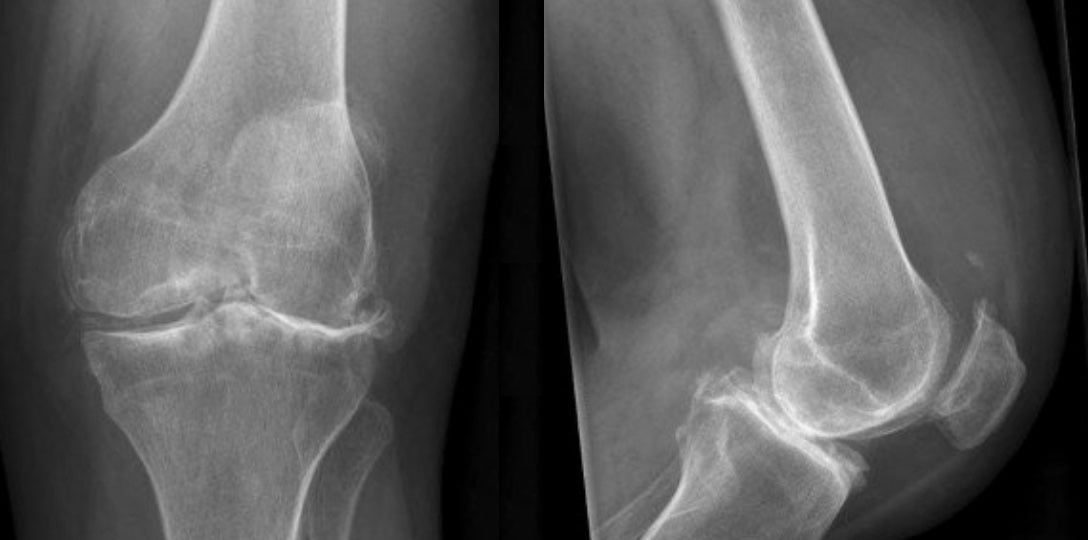

- X-ray images can reveal joint space narrowing, bone spurs, and other changes associated with arthritis as well as providing important information about your bony alignment.